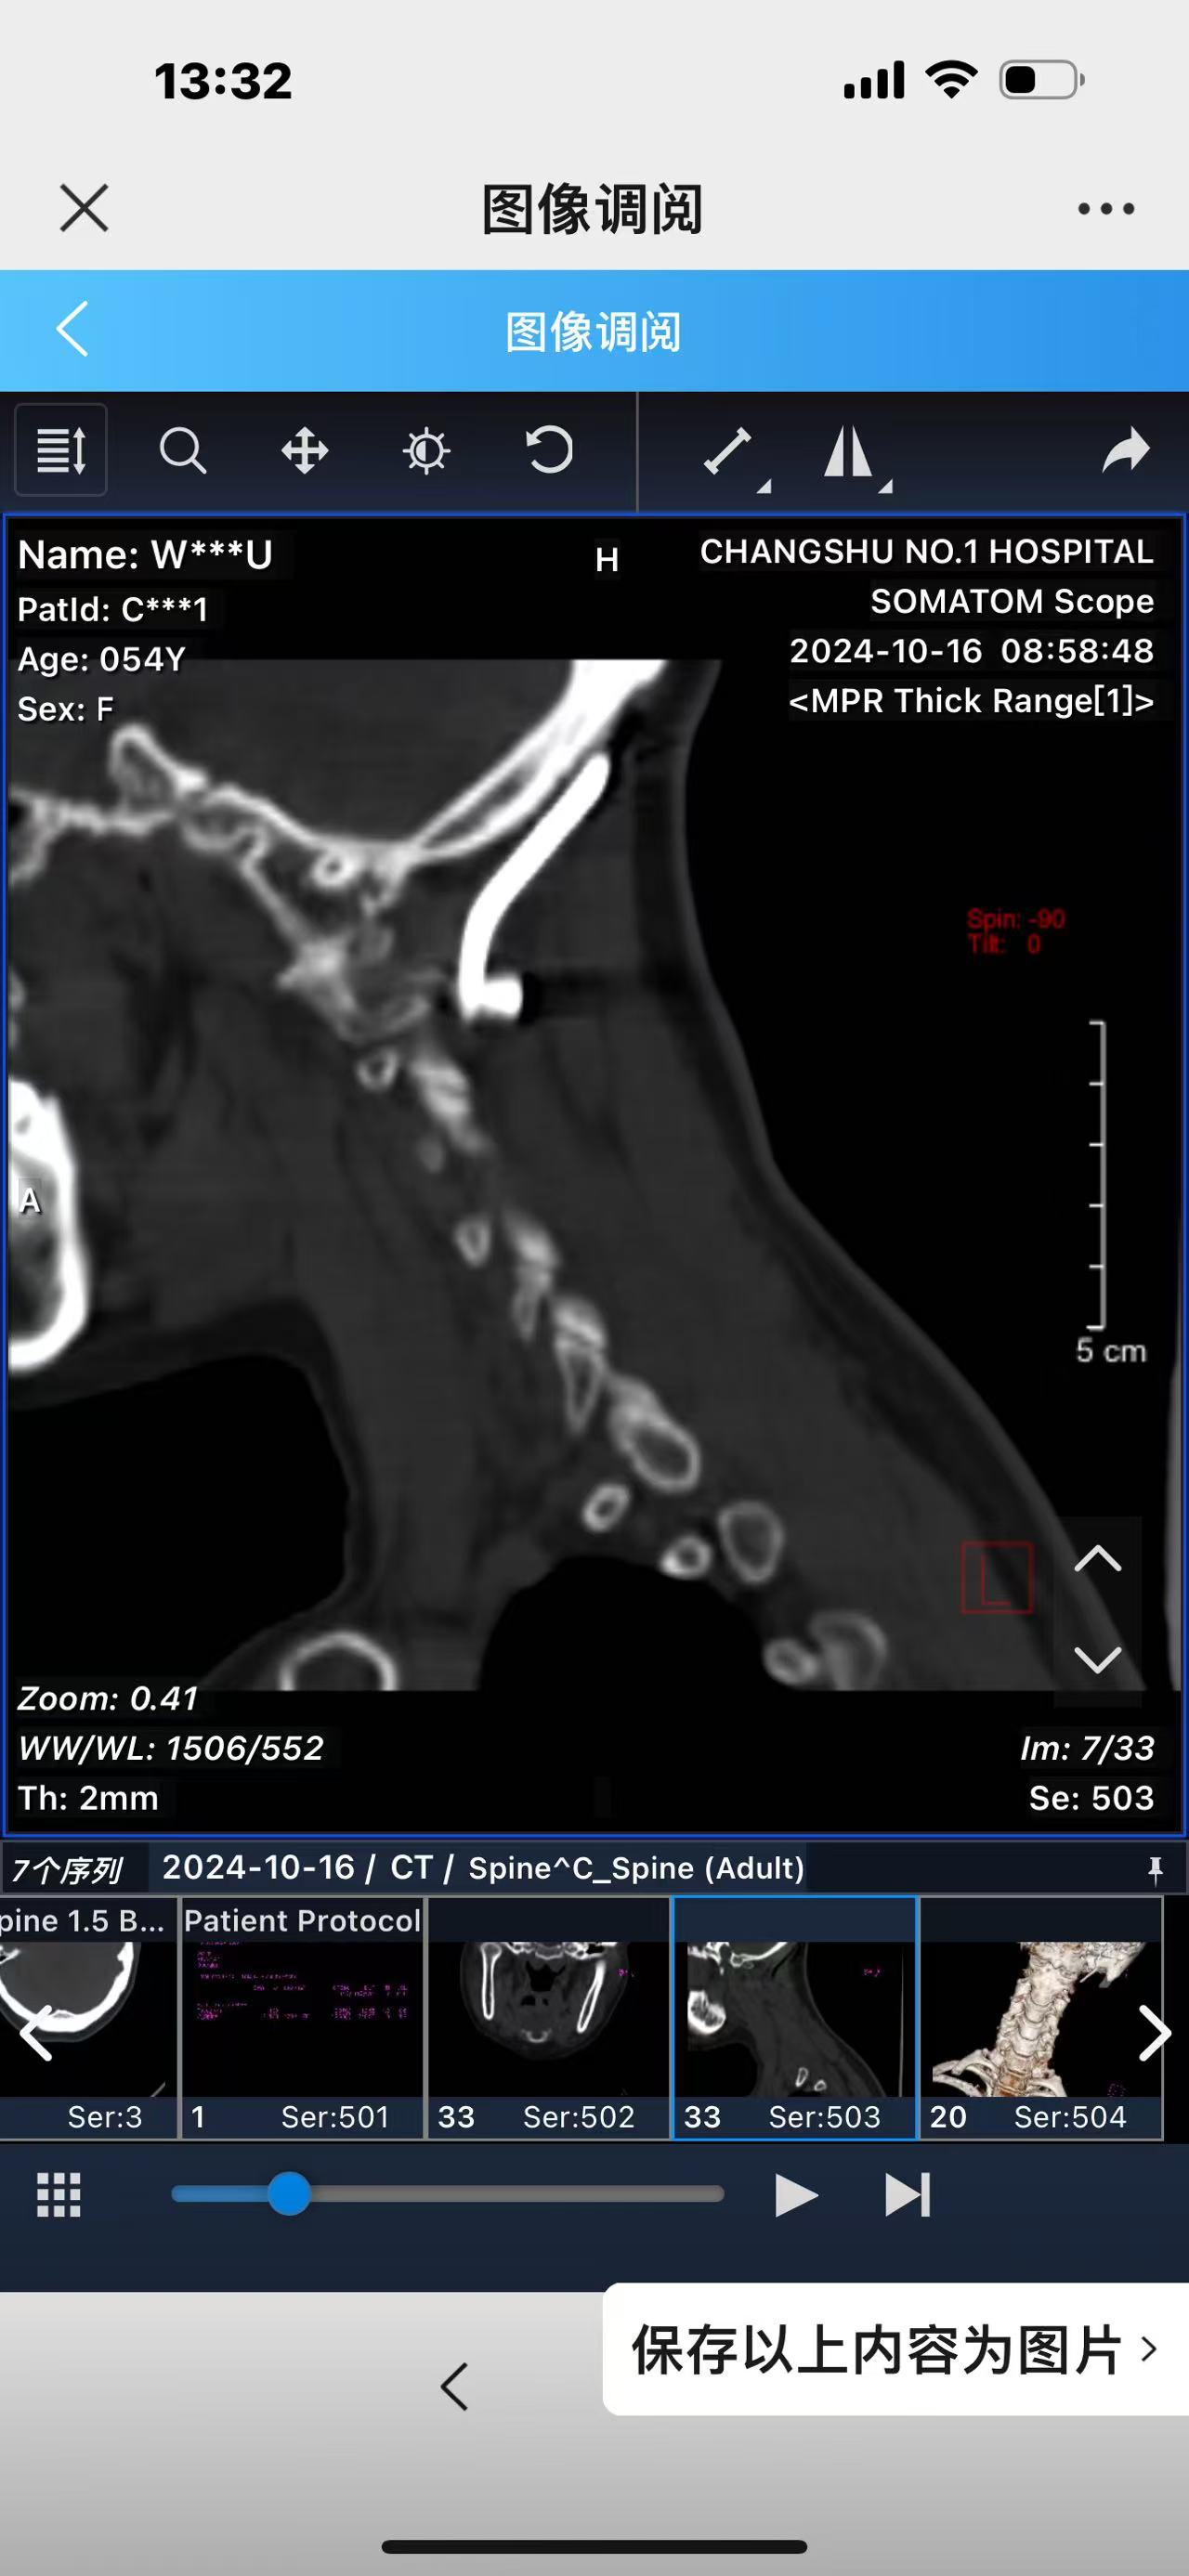

• 诊断:寰枢椎脱位,颅底凹陷

• 影像:

• 术后影像: